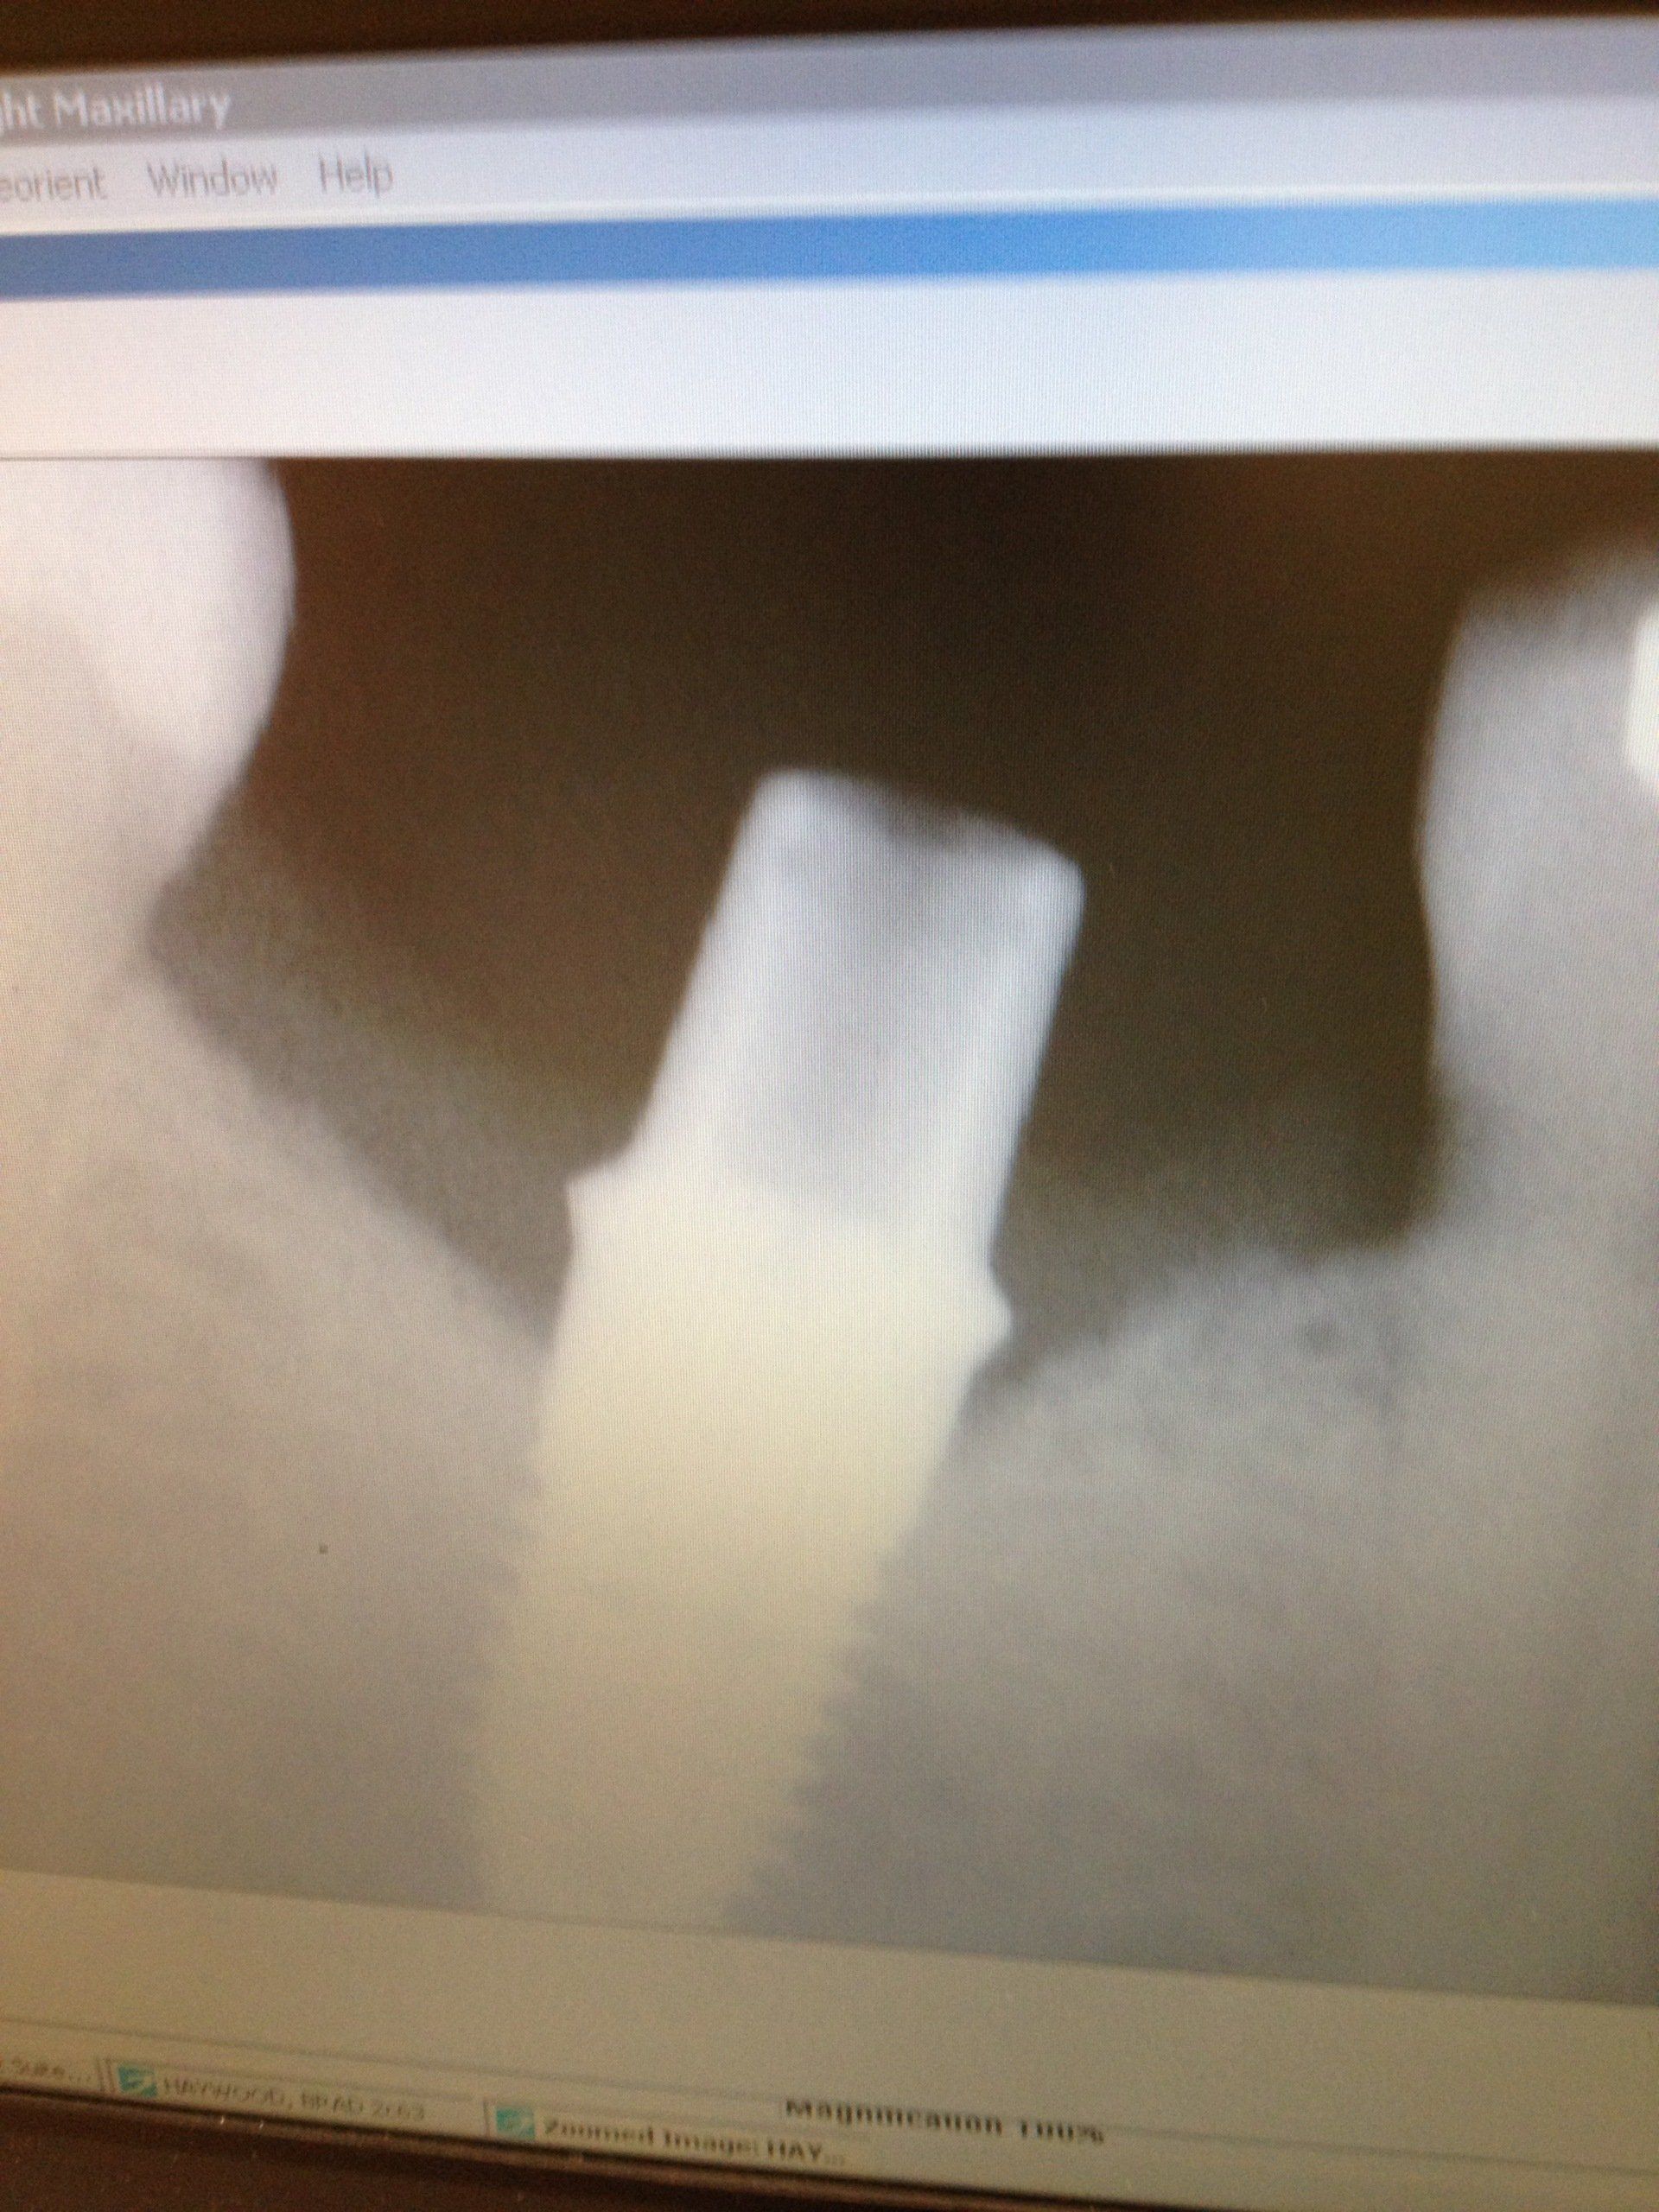

Gallery

A healthy and radiant smile is the goal. We offer dental care and

information on how you can prevent any diseases.